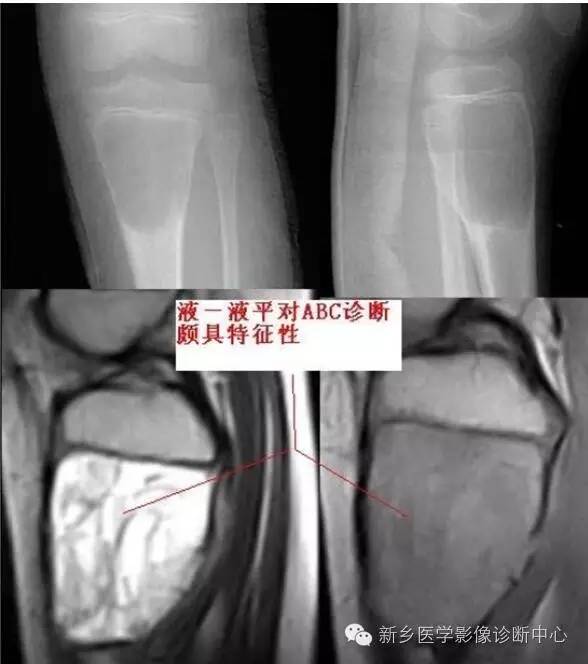

动脉瘤样骨囊肿 好发于30 岁以下青年人;部位以长骨干骺端、骨盆、脊柱多见;临床多以局部肿胀、疼痛就诊;多有外伤史。病理上多位于骨松质、髓腔中央,少数位于皮质及骨膜;充满深红色、棕红色不凝固血液;单房或多房,有纤维骨性间隔。

偏心、吹出样膨胀性、多房或单房溶骨改变,皮质受压变薄,边界清楚伴硬化。MRI 囊液呈长T1 长T2 信号,纤维骨性间隔T1T2 均为低信号;病灶内有液液平面(T1 上低下高,T2 上高下低),较具特征性。

读片要点:1、10-20 岁多见,长骨以干骺端多见2、长径与骨干平行3、很少累及关节面4、膨胀一般较明显,呈“吹出气球样”,膨胀明显可见骨膜反应,囊间隔可有钙化5、边缘光整伴硬化6、多有外伤史